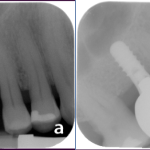

A sinus lift is surgery that adds bone to your upper jaw in the area of your molars and premolars. It’s sometimes called a sinus augmentation. The bone is added between your jaw and the maxillary sinuses, which are on either side of your nose. To make room for the bone, the sinus membrane has to be moved upward, or “lifted.” A sinus lift usually is done by a specialist.

Your surgeon will cut the gum tissue where your back teeth used to be. The tissue is raised, exposing the bone. A small, oval window is opened in the bone. The membrane lining the sinus on the other side of the window separates your sinus from your jaw. This membrane is gently pushed up and away from your jaw.

Granules of bone-graft material are then packed into the space where the sinus was. The amount of bone used will vary, but usually several millimeters of bone is added above the jaw.